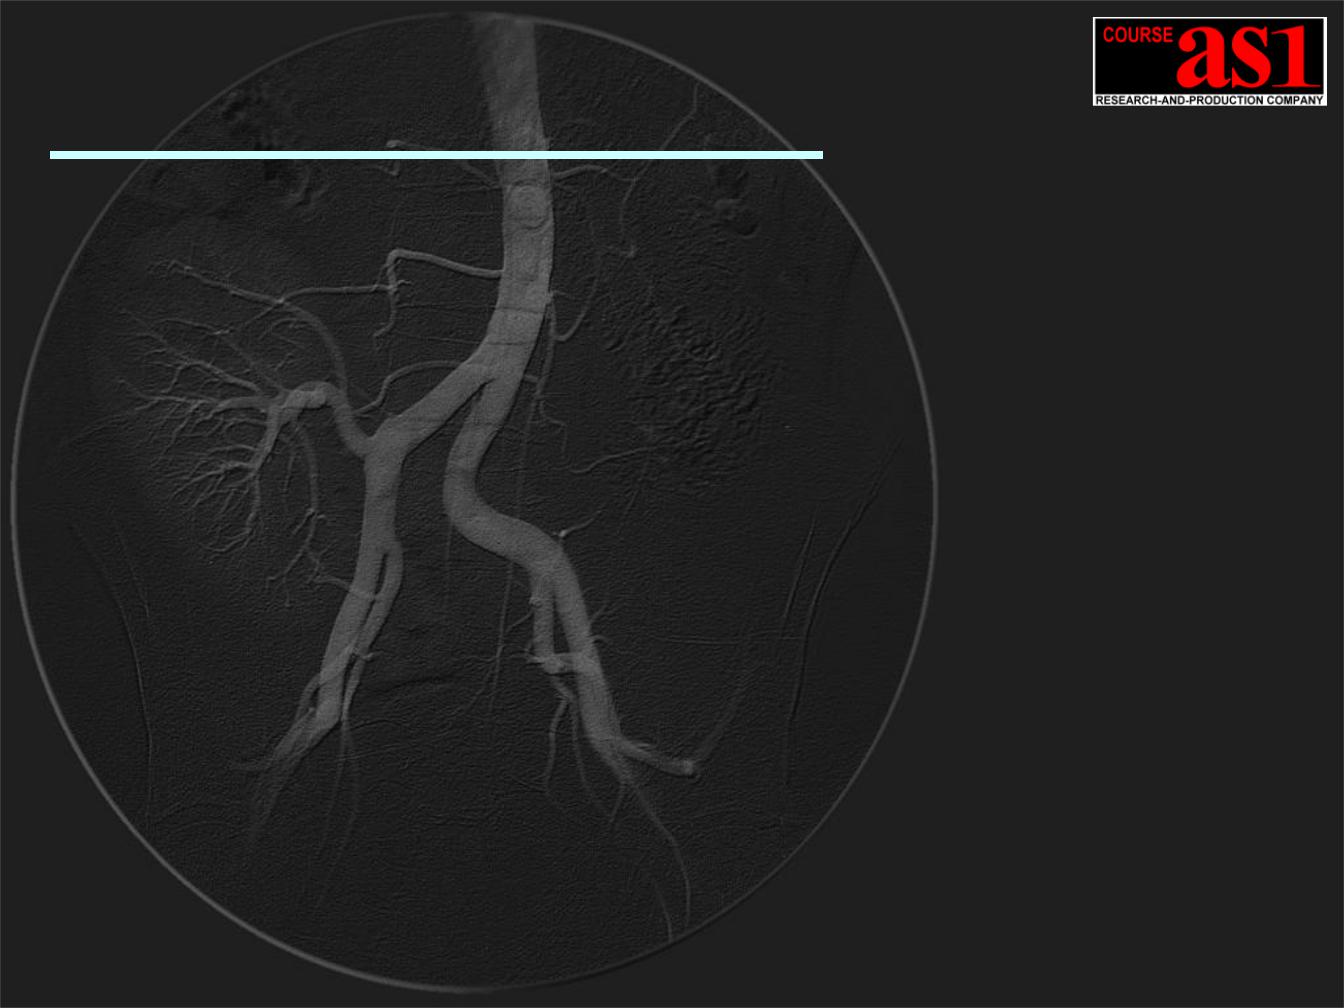

Проект – “100 микрон”

Ангиографическая Система Сверх Высокого Разрешения с Потоковой 2D Обработкой и Визуализацией Реального Времени (1080 MB/s)

с интегрированным Компьютерным X-Ray Томографом Сверхвысокого Разрешения.

-10.5(12.0) / 2.1(3.0) Мегапикселей при 60/120 кадр/сек.

-Формат поля 300(400)x300 mm / 100 mkm пиксель /

Снижение рентгеновской дозы в 20 раз!! Аналогов не существует !!